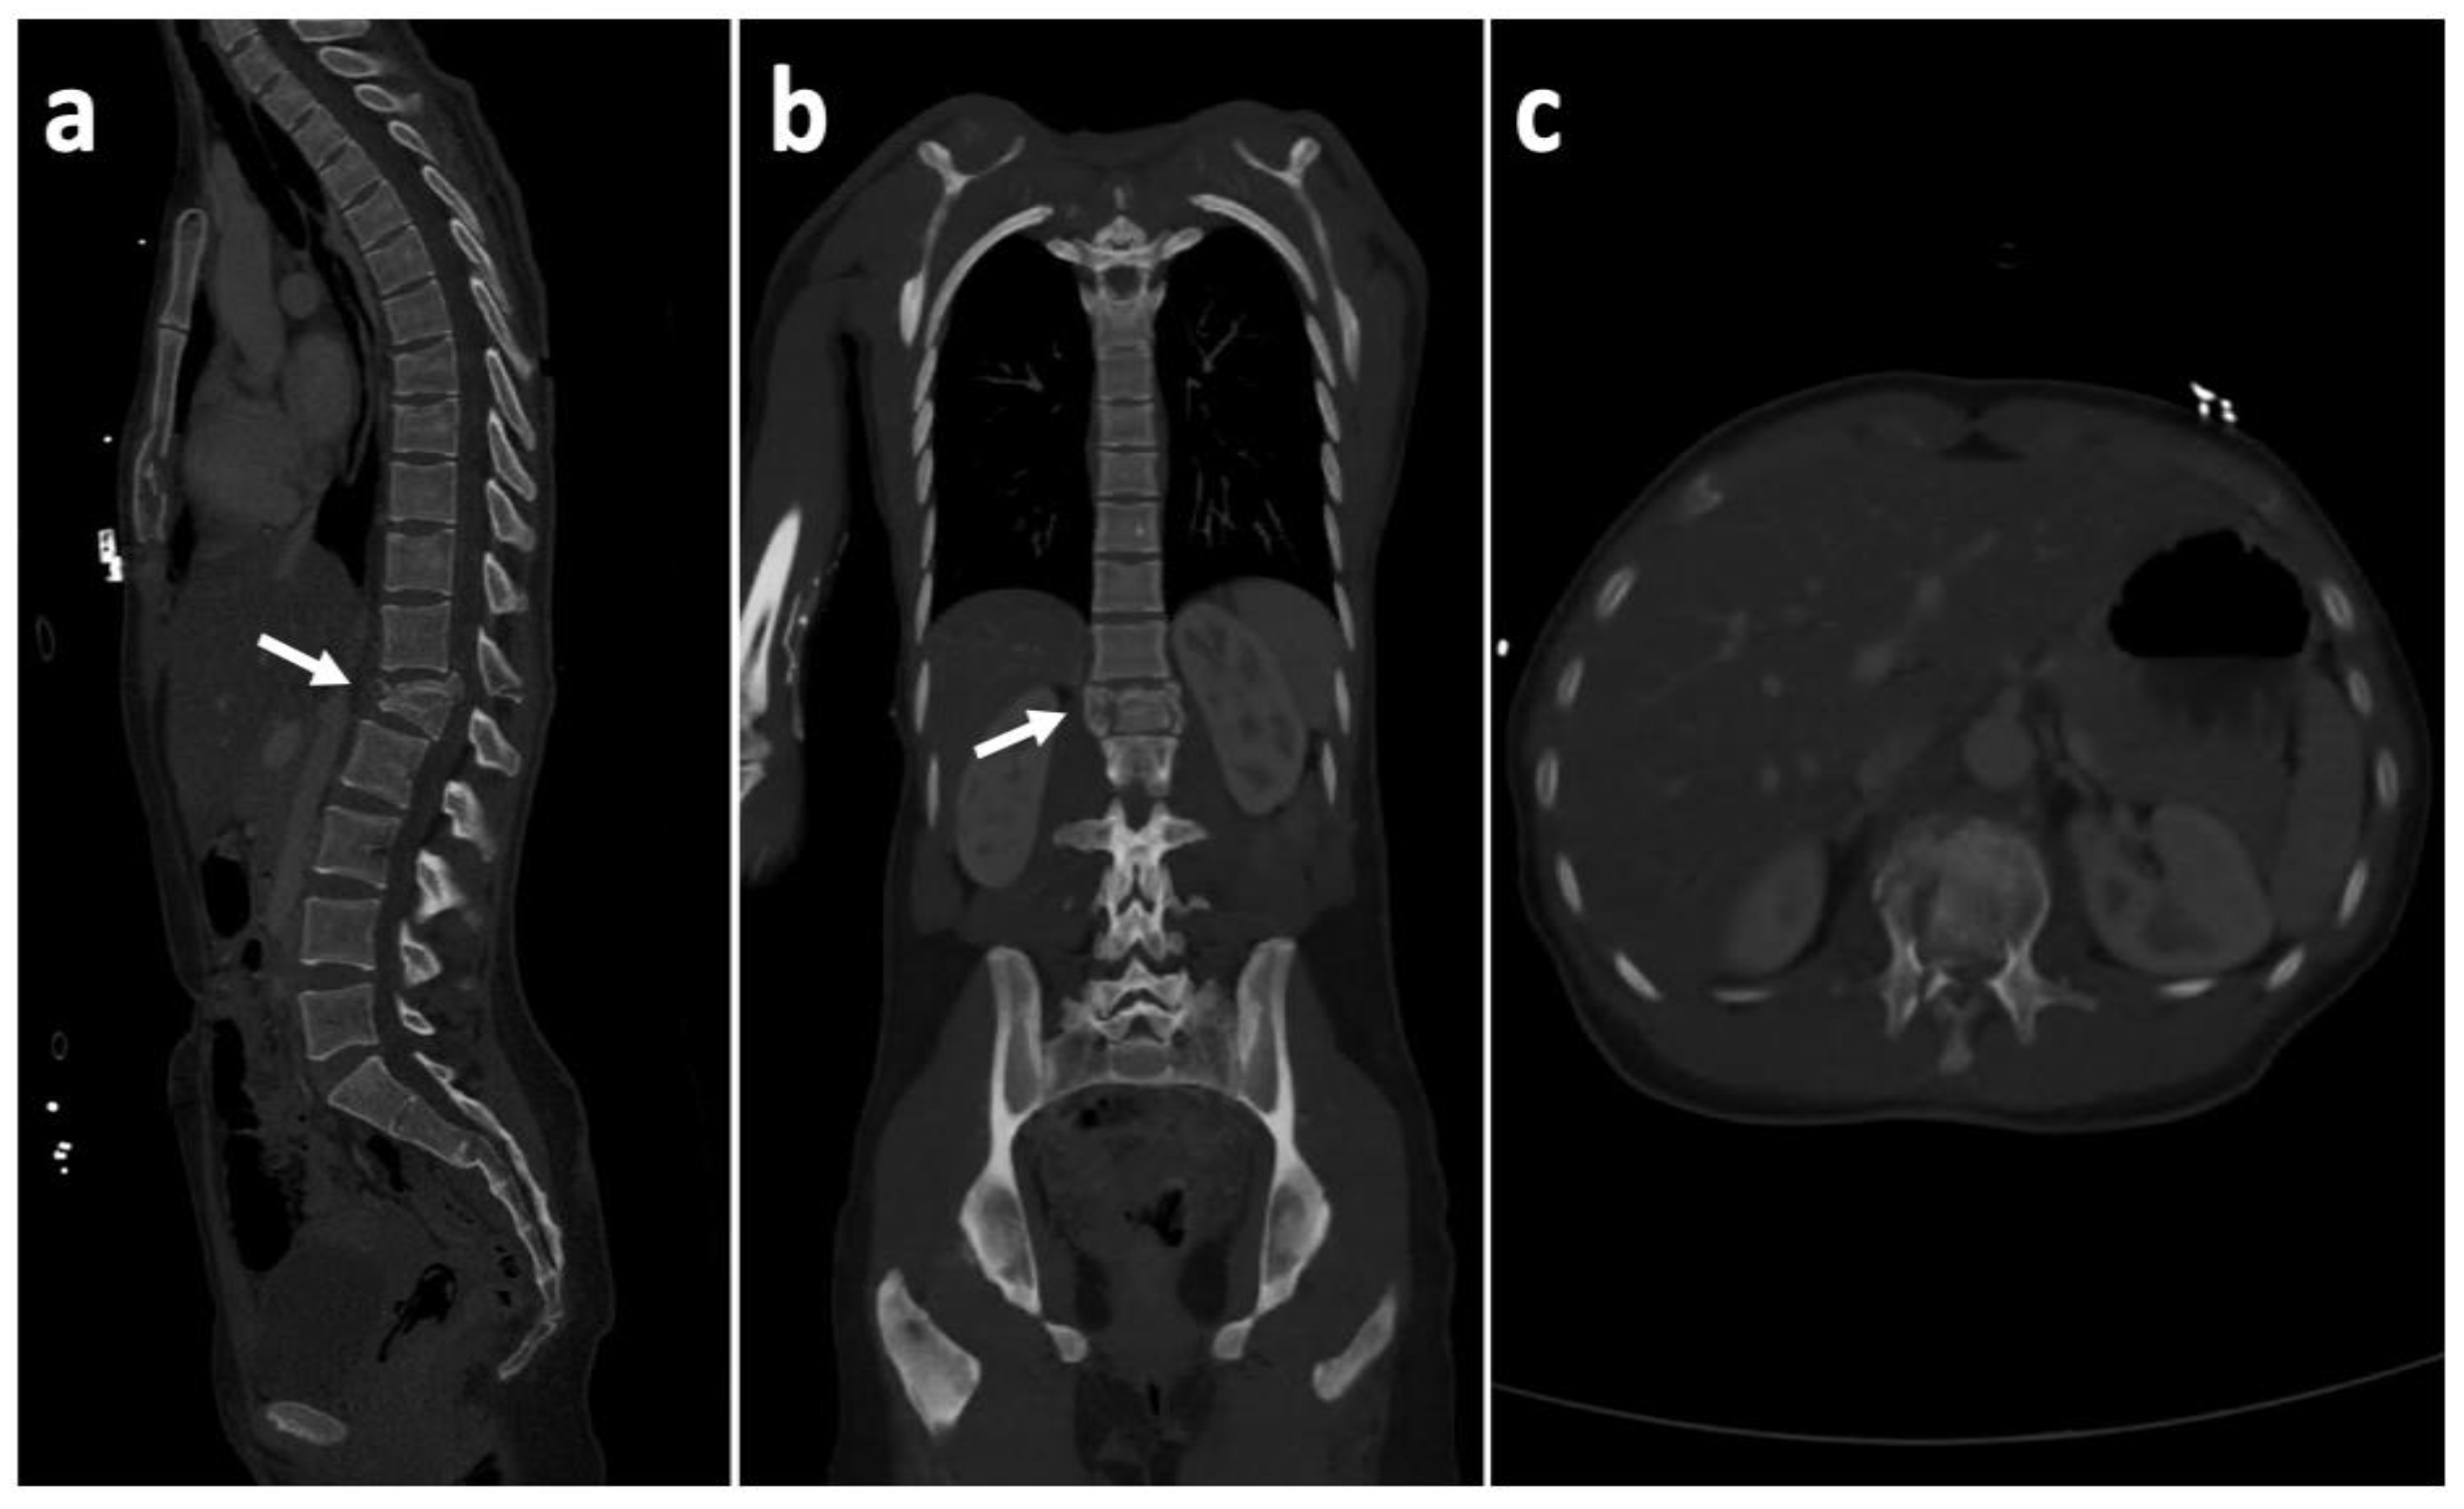

2. Case History